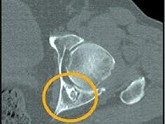

- 单项选择题患者40岁,男性, 如图所示,最可能的诊断是 ( )

A、骨样骨瘤

B、转移瘤

C、内生软骨瘤

D、软骨肉瘤

E、以上都不是